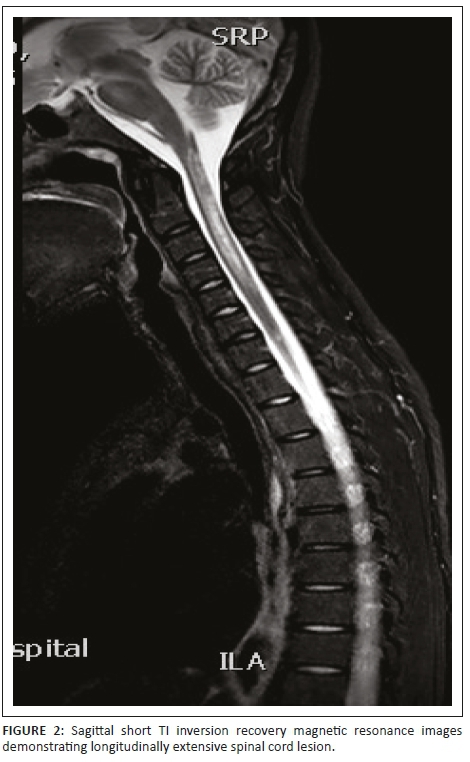

Magnetic resonance imaging of the cervical spine revealed a T2 hyperintense central grey matter lesion extending longitudinally and contiguously across three vertebral body lengths. Brain MRI demonstrated similar T2 hyperintense lesions involving the splenium of the corpus callosum, the midbrain and centrum semiovale. There were no perivenular radially oriented lesions (Dawson fingers) that are typical of MS.

Spinal cord imaging features in NMO demonstrate the presence of longitudinally extensive spinal cord lesions (LESCLs), which extend contiguously across at least three vertebral segments.2,3,4 LESCLs are, however, not exclusive to NMO and appear to be less disease specific in children than in adults. They are frequently observed in children with acute disseminated encephalomyelitis, as well as in 17% of those with MS and in 67% - 88% of those with monophasic transverse myelitis.5,6 In NMO there is a preferential involvement of the central grey matter which is abundant with AQP4 in the glial cell processes adjacent to the ependymal cells of the central canal with lesions frequently affecting the cervical and thoracic spinal cord.3,5 Lesions in NMO exhibit high signal intensity on T2-weighted images and low signal intensity on T1-weighted images.